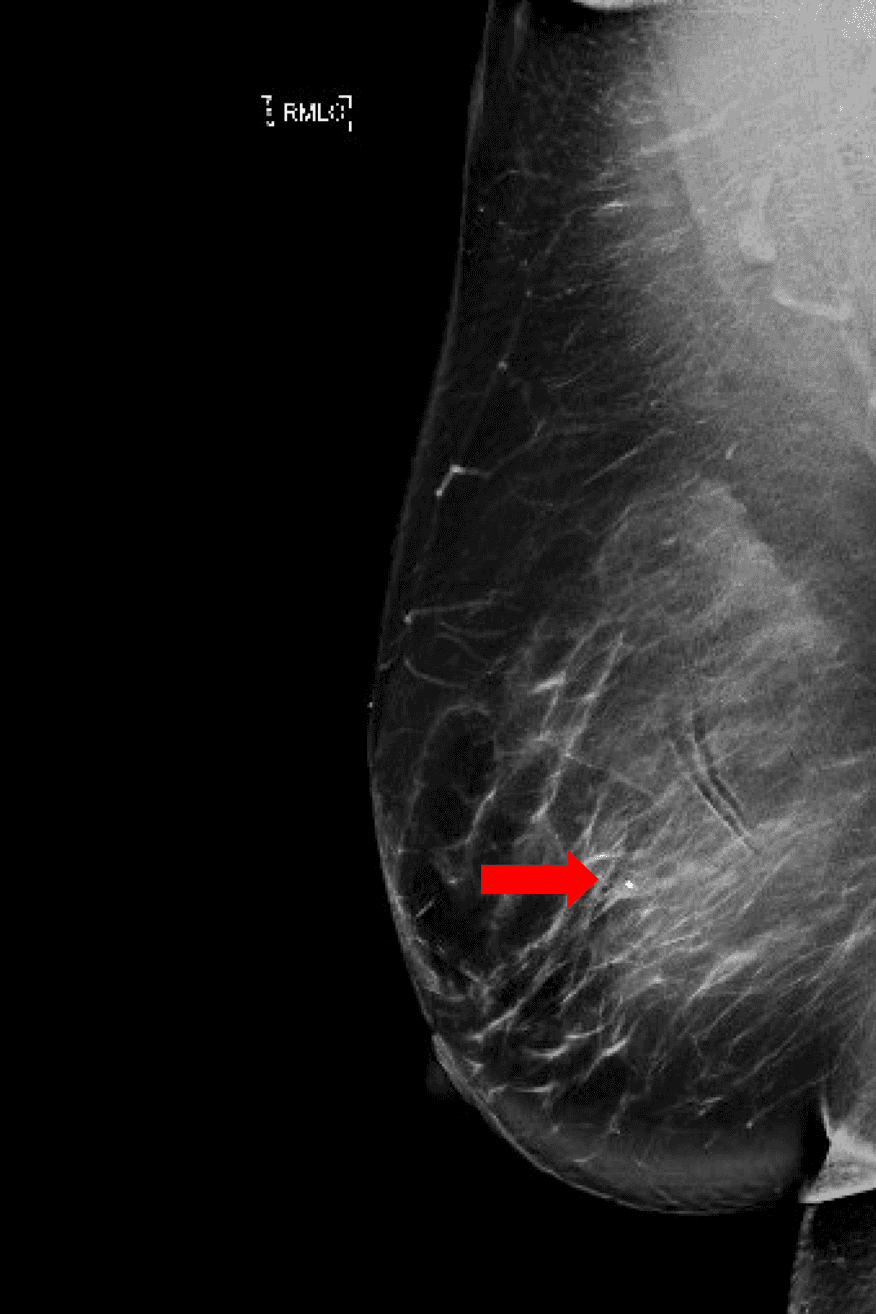

Patient is a 46-year-old premenopausal female with no other contributing past medical or surgical history who presented initially to the breast surgery clinic after her annual screening mammogram discovered a nonpalpable right breast mass measuring 0.6 x 0.8 x 0.7 cm at 11 o’clock (oc), 1 cm from the nipple (FTN) (Figure 1). She had three previous screening mammograms without any notable findings. The screening mammogram was declared inconclusive (BI-RADS 0), and a breast ultrasound was completed with similar findings. Further discussion with the patient revealed that there had been some bloody discharge seen in the right side of her bra over the last few months, but no other concerns or symptoms. Given the inconclusive imaging findings, it was decided to perform a diagnostic mammogram for a more specific assessment (Figures 2a and 2b) following an ultrasound-guided core-needle biopsy and localizing clip placement for a tissue diagnosis (Figure 3). Pathology revealed an intraductal papilloma with ductal hyperplasia and apocrine metaplasia without atypia. Given her continued bloody nipple discharge, there was concern for possible underlying premalignant cells (discussed more later); thus, it was recommended that the patient undergo partial mastectomy. The mass remained nonpalpable; therefore, a Savi Scout would be placed just before operative intervention to help localize the area of concern.

Figure 2b. Craniocaudal view of the post-biopsy diagnostic mammogram. Including a closer image of the area with the coiled biopsy clip (arrow).